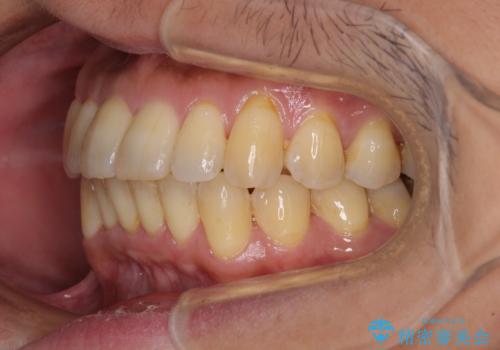

前歯のデコボコ ワイヤー装置での短期間治療

治療開始の頃は、食事や歯磨きが慣れず、装置が頻繁に脱落しましたが、2,3ヶ月ほどで慣れ、その後は1年ほどで治療を終えることができました。